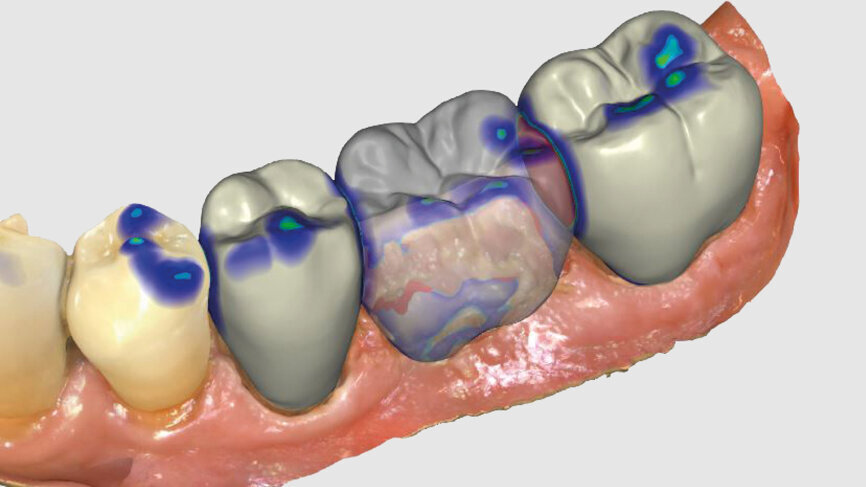

One week later, the extraction socket, which was still healing, was modelled for the ovoid pontic using an electrotome loop. The second premolar and molar were prepared as abutment teeth for a bridge. The bridge was then designed (Figs. 4–6) and milled from KATANA Zirconia Block for Bridge in Shade A3.5 and individualised with CERABIEN ZR FC Paste Stain (both Kuraray Noritake Dental; Figs. 7–10). A further week later, the bridge was luted with the self-adhesive resin cement PANAVIA SA Cement Universal after sandblasting (Figs. 11–13).

Fig. 4: Bridge design using CEREC Software.

Fig. 5: Bridge design using CEREC Software.

Fig. 6: Owing to the bright shade of the teeth in the cuspal area, the restoration was positioned high in the multilayered KATANA Zirconia Block.